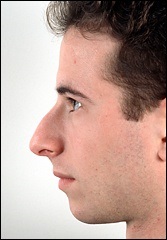

A fénykép a bal oldalon mutatja egy ember tipikus megnövekedett nazális gerinc. Ez jelentősen növeli az orrát előre. A fénykép után a művelet ugyanaz az ember nagyon jól néz ki.

Ebben a beteg, ott van a hatás a „kötés” a felső ajak. Photo fenti elégedett üzemeltetés előtt. Fekete jelzi a helyzetét az első kiálló orr-gerinc. A kék vonalat húzott a jobb megítélése a profilt. Ha a hatása „árukapcsolás” a felső ajak vonal irányította a profilját Vered és legfeljebb az alap az orr.

A férfi látható a felső képen látható jól látható összes következményét a hosszúkás elülső orr-gerinc: határozottan kiálló orr, „kapcsolt” a felső ajak és columella túl nyitott. Azonban meg kell jegyezni, hogy az oka ezeket a „következmények” nem csak vetített előre az orr gerinc.